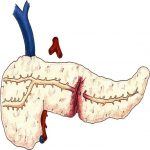

Chấn Thương Tá Tụy | Bài giảng CĐHA

Chấn thương tụy – tá tràng là bệnh lý hiếm gặp trong chấn thương bụng kín, chiếm 3-15% chấn thương bụng. Khối tá tụy nằm sau sau phúc mạc, chẩn đoán thường muộn do triệu chứng ban đầu kín đáo, dễ bỏ sót, dẫn tới biến chứng nặng…